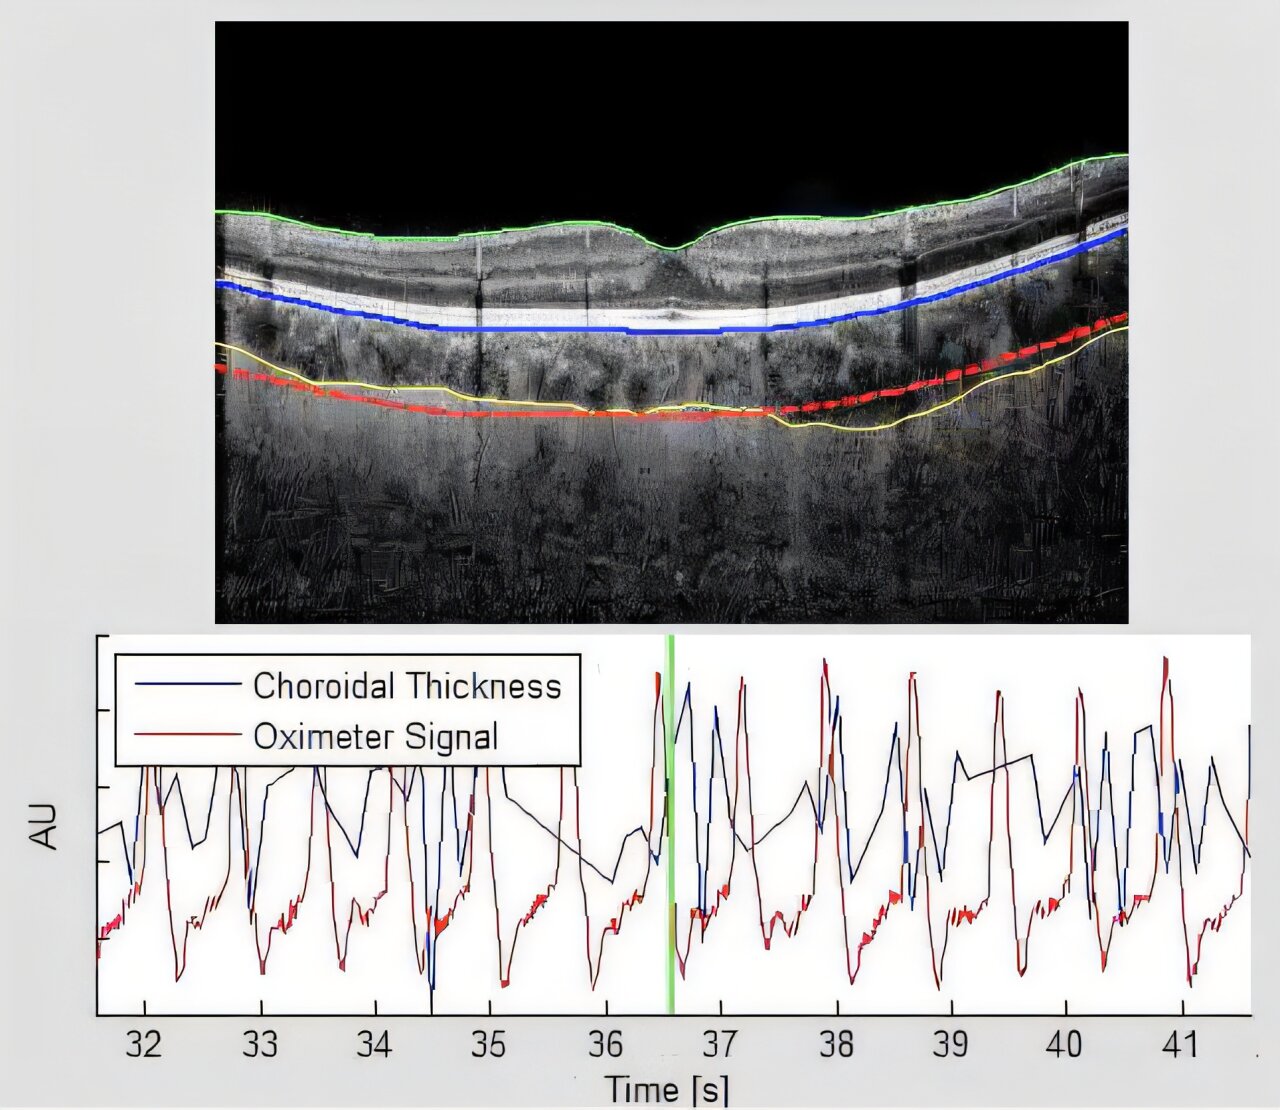

SANSORI, a CSA (Canadian Space Agency) investigation, used an imaging technique called Optical Coherence Tomography to examine whether reduced stiffness of eye tissue contributes to SANS. On Earth, changes in stiffness of the tissue around the eyeball have been associated with aging and conditions such as glaucoma and myopia. Researchers found that long-duration spaceflight affected the mechanical properties of eye tissues, which could contribute to the development of SANS. This finding could improve understanding of eye changes during spaceflight and in aging patients on Earth.

The Fluid Shifts investigation, conducted from 2015 through 2020, was the first to reveal changes in how blood drains from the brain in microgravity. Vision Impairment and Intracranial Pressure (VIIP) began testing the role those fluid shifts and resulting increased brain fluid pressure might play in the development of SANS. This research used a variety of measures, including clinical eye exams with and without dilatation, imaging of the retina and associated blood vessels and nerves, noninvasive imaging to measure the thickness of retinal structures, and magnetic resonance imaging of the eye and optic nerve.